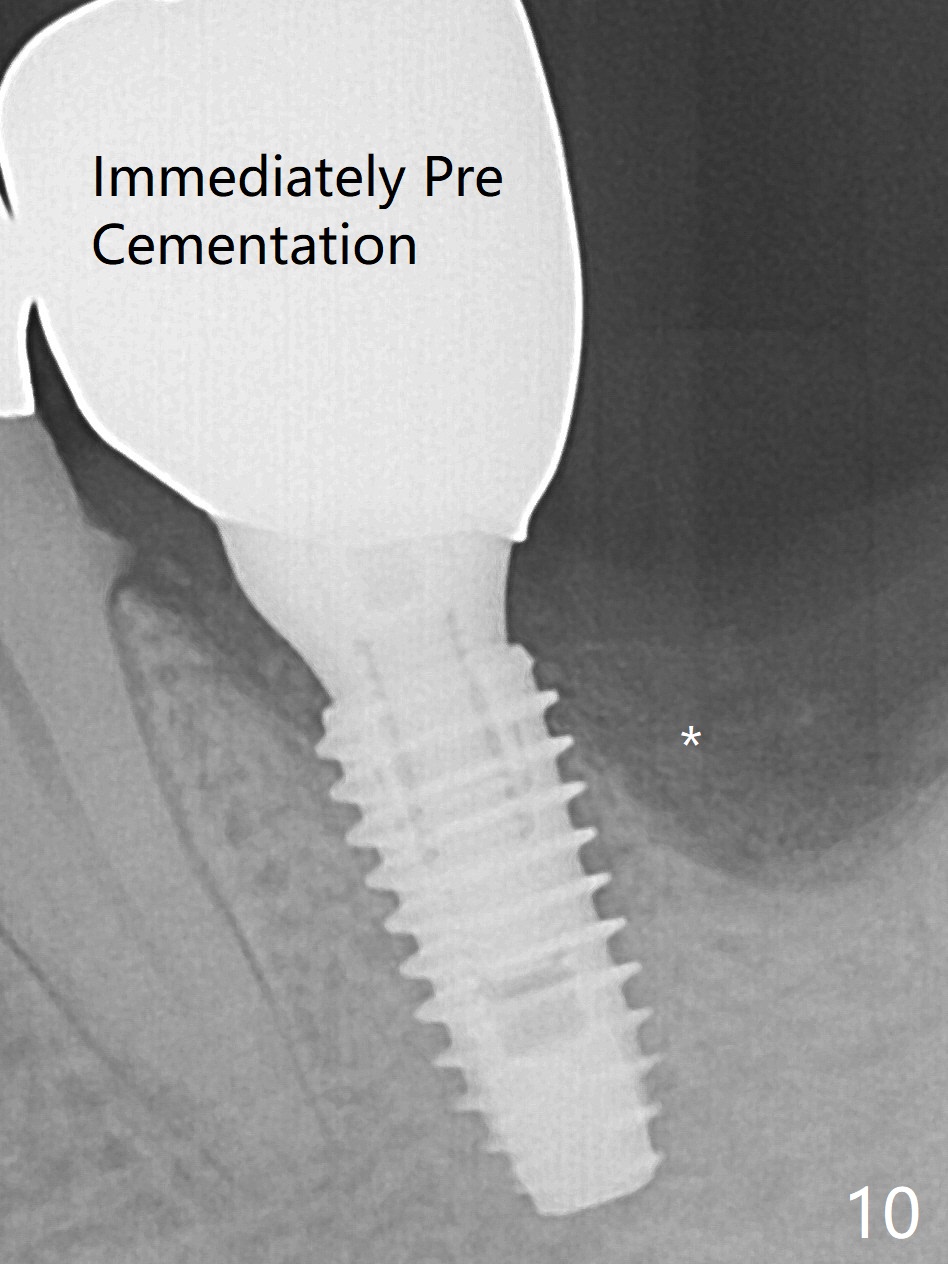

There is shrinkage in the mesial alveolus 1 month postop (Fig.6 *). When the provisional is removed 2 months postop, there is minimal amount of unincorporated bone graft (Fig.7 G) and Osteogen Plug (M, membrane). As the un-attached materials are washed up, the distal socket heals without exposure of implant threads (Fig.8 D). The bone graft settles down and remains in the distal socket 2.5 months postop (immediately pre-cementation, Fig.10 *). The bone graft appears to prevent implant threads from being exposed 2 months post cementation (Fig.11). The bone density in the distal socket increases significantly 8 months post cementation (Fig.12 *).